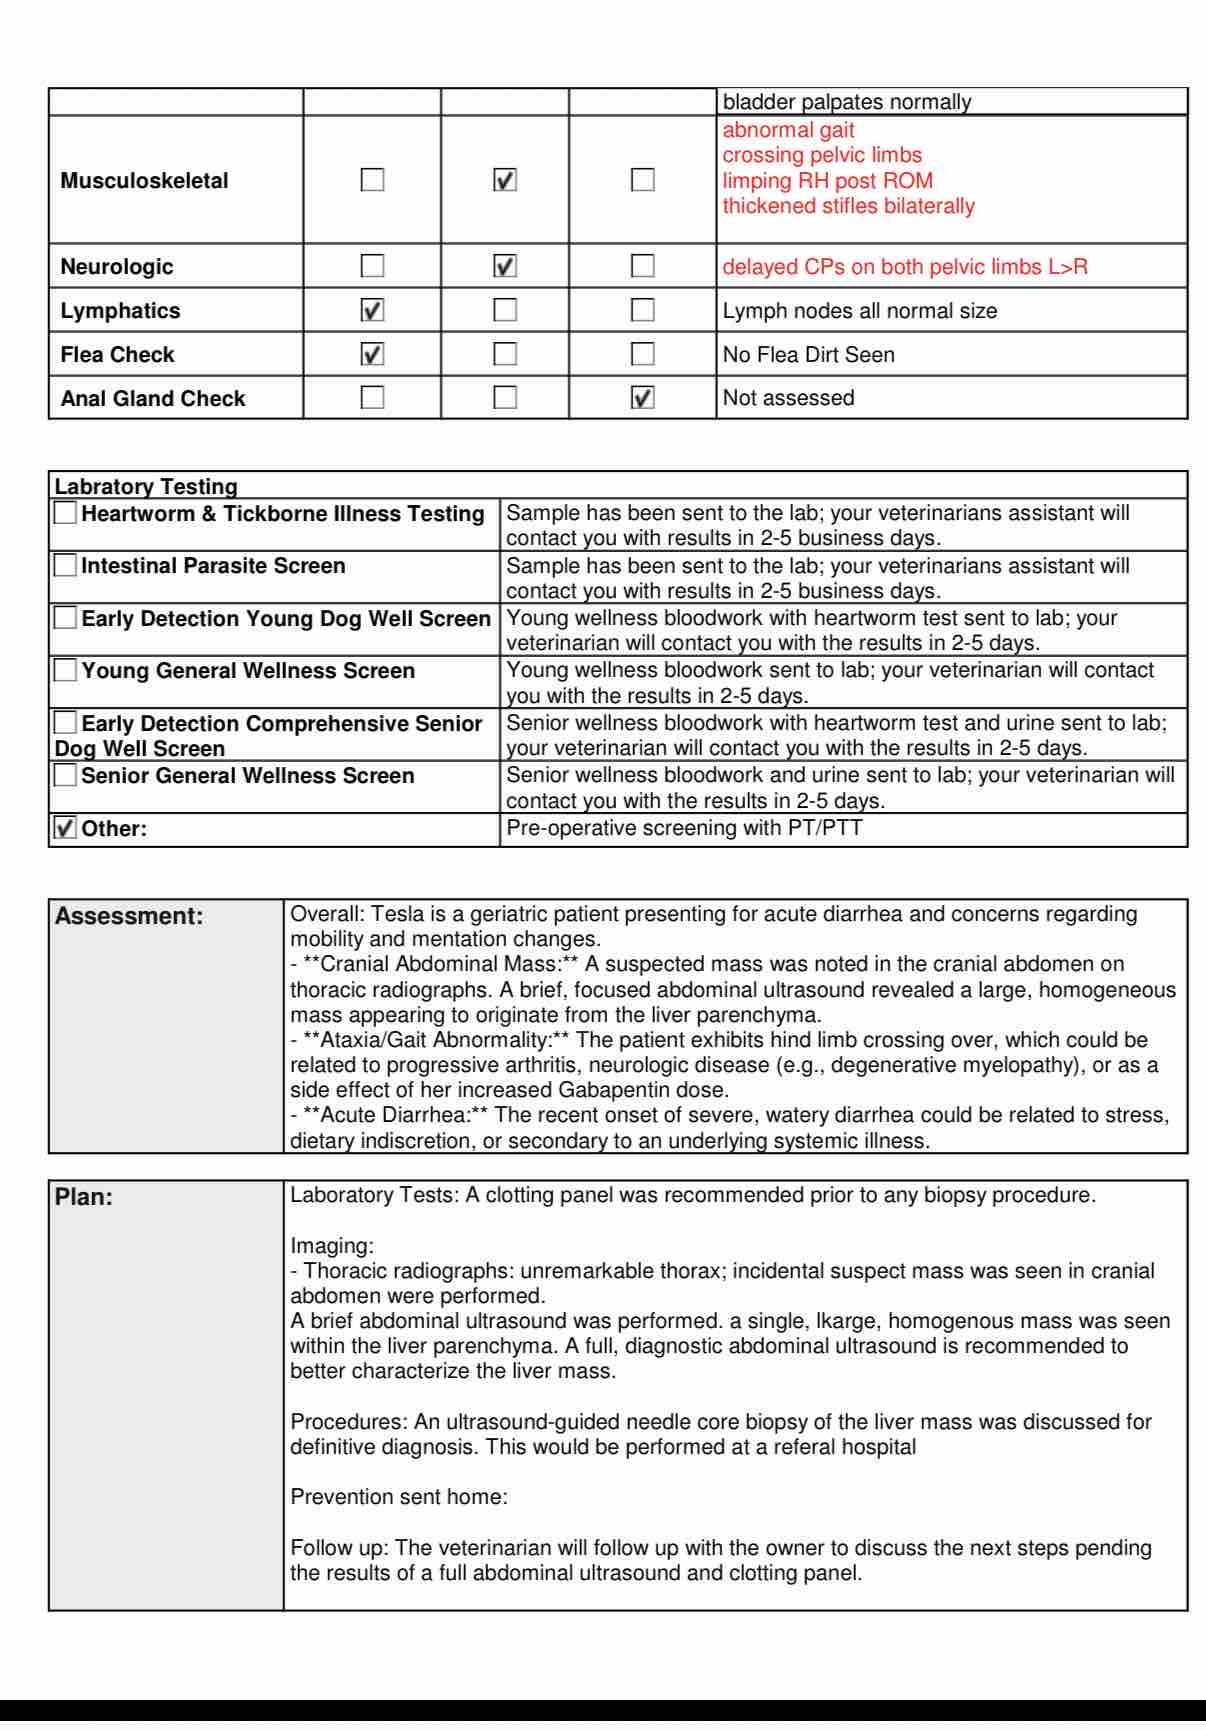

Tesla is my life, and recently she was diagnosed with a large liver tumor, likely cancer. The news caught me completely off guard, and the tumor is already squishing her organs. There are many steps ahead in this journey, and last week was just the beginning. On May 4, we'll learn much more—like whether she's a candidate for a potential lobectomy, which could give her a chance at recovery.

Anyone who knows me knows how much I love Tesla. I never ask for help, but right now, I am scared and overwhelmed. I've already spent a lot on diagnostic testing and blood work needed for a biopsy. The internists at Med Vet quoted a significant amount for a consult, full abdominal ultrasound, and biopsy of her liver tumor. This is a fluid situation, and I've missed days of work to care for her. Supporting us by myself, I am reaching out for help because anything you can give is greatly appreciated.